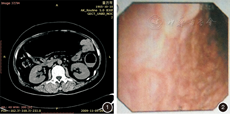

例1 患者女,44岁,因"突发下腹痛7 h"收住我院。患者无明显既往病史,入院前7 h突发下腹痛,伴肛门停止排便排气。入院时查体仅见左下腹部压痛,无反跳痛及肌卫,肠鸣音稍亢进。血常规示白细胞计数(WBC)29.0×109/L、中性粒细胞百分比(N)91.5%、血小板计数(Plt)150×109/L。CT及腹部立位片示横结肠明显扩张(图1)。肠镜检查见直肠至肝曲连续性病变,肝曲至回盲部及回盲瓣未见异常,病变处结肠袋结构消失,结肠壁呈颗粒样,组织高低不平,弹性差,呈铅管样改变(图2);病理示黏膜活动性炎伴溃疡形成,考虑溃疡性结肠炎。予抗感染、补液、支持、肾上腺皮质激素等治疗后,腹痛不缓解且渐加重,伴高热,查体下腹压痛及反跳痛明显,腹穿抽出淡血性液体,心率增快达150次/min,并出现败血症。立即转普外科行"全结肠切除、回肠-直肠吻合术",病理提示符合溃疡性结肠炎。随访5年至今患者情况良好。诊断为"溃疡性结肠炎,中毒性巨结肠"。